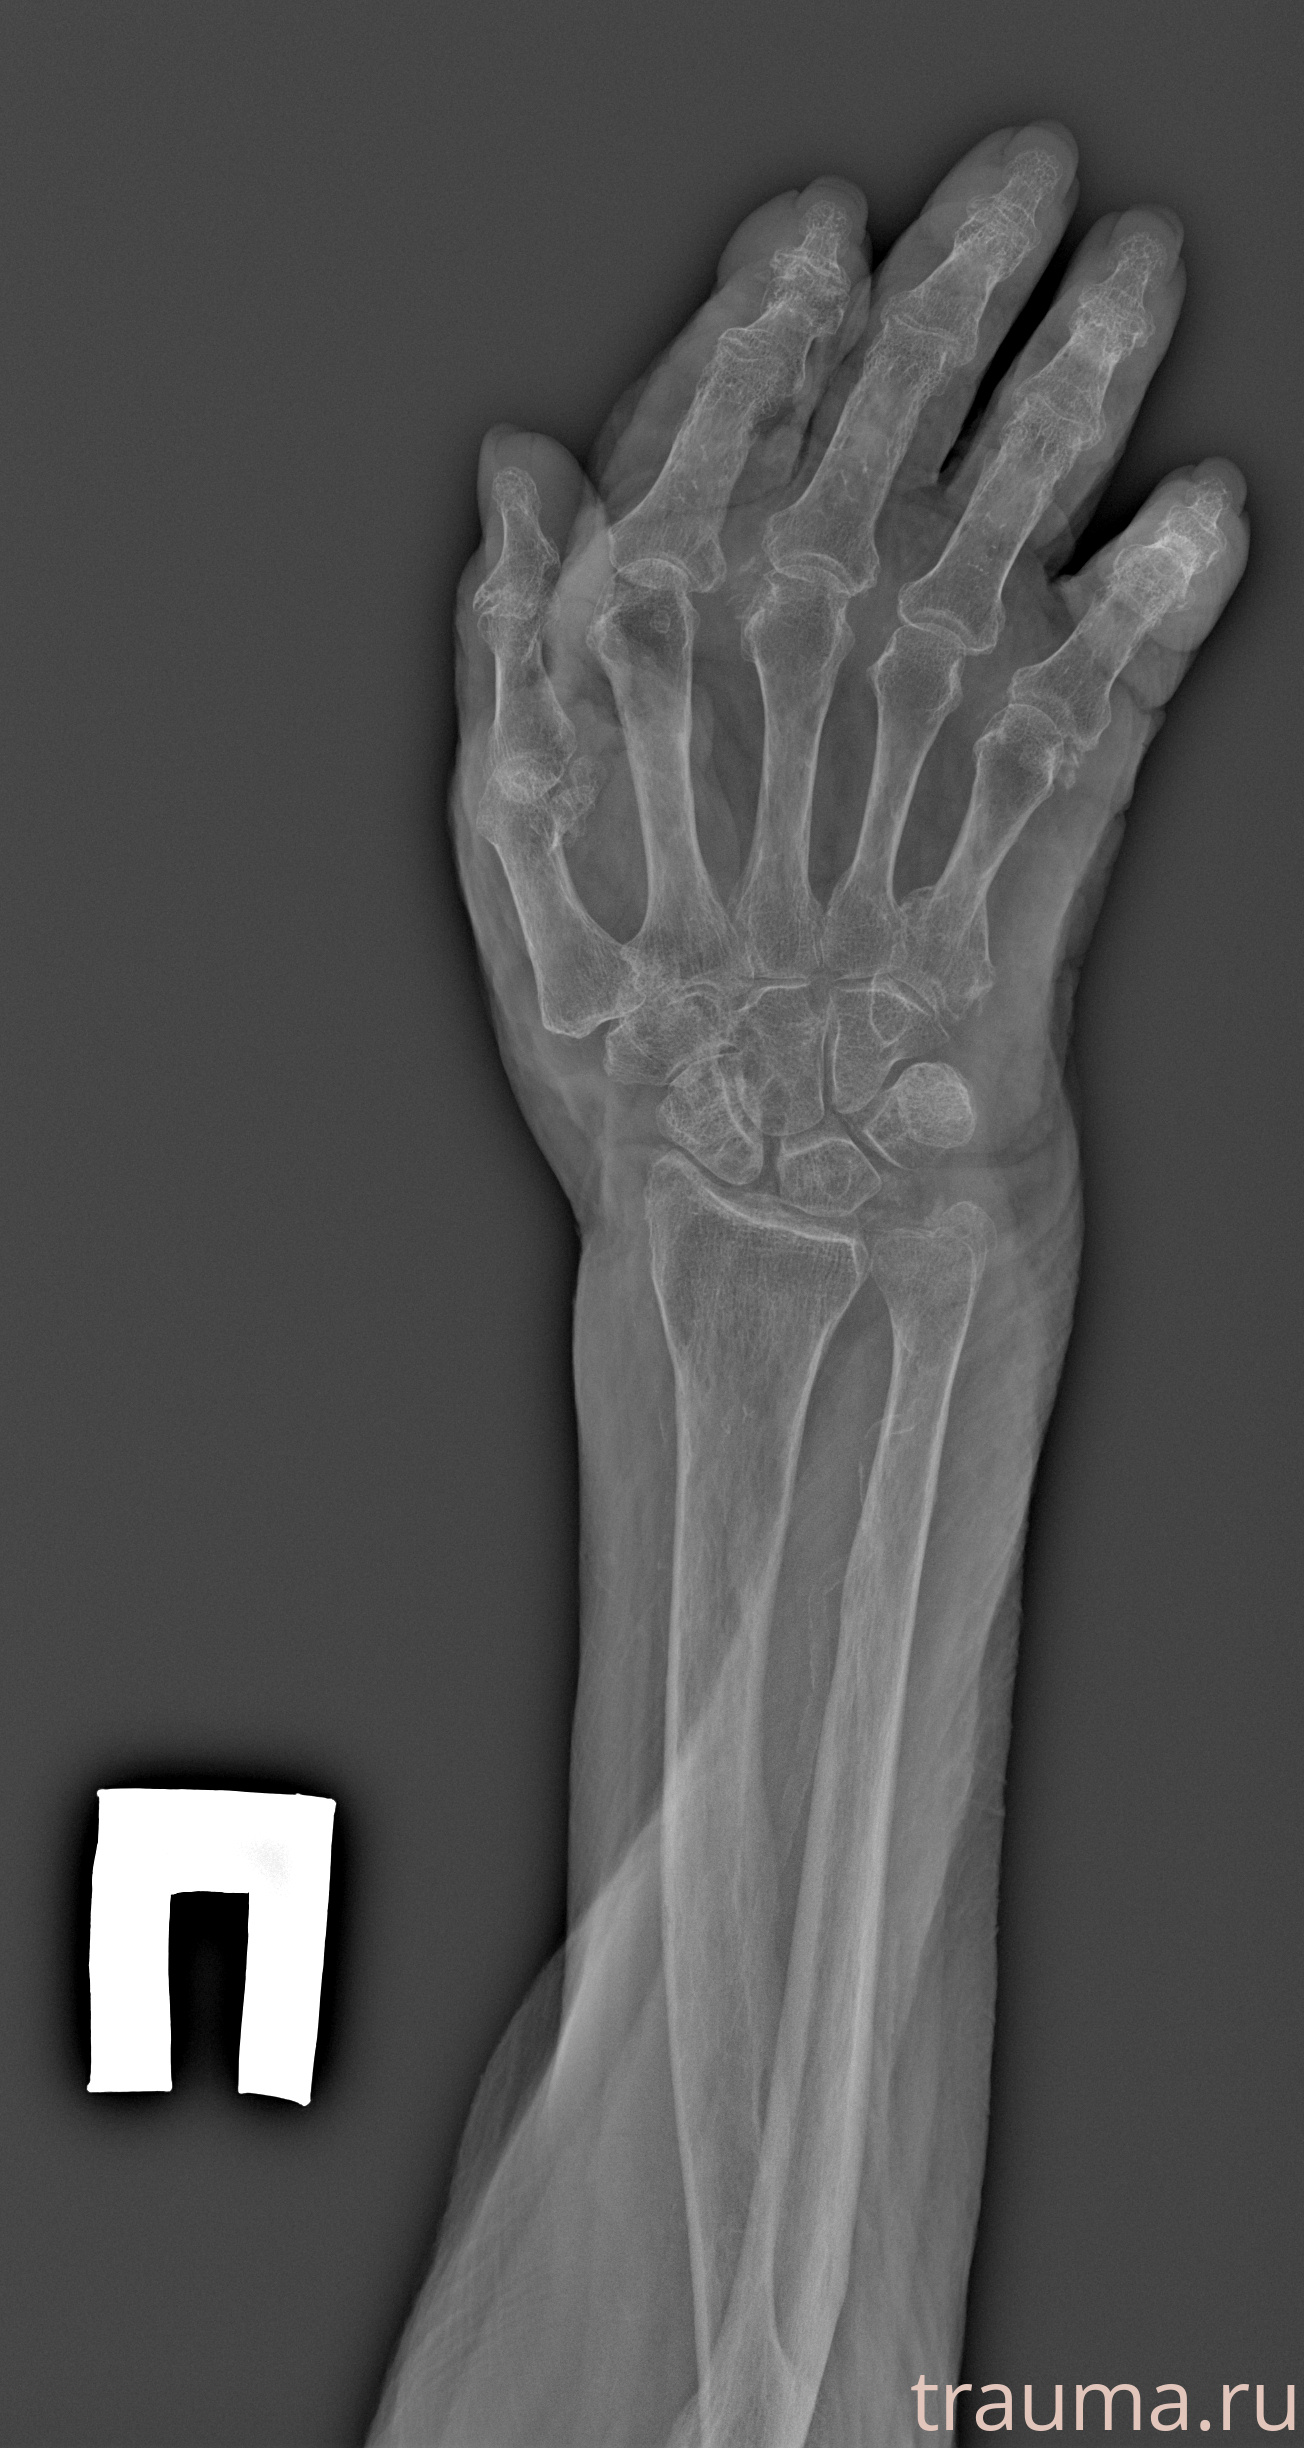

Рентген на дому: по вашему адресу приезжает врач-рентгенолог, травматолог-ортопед с мобильным рентгеновским аппаратом, проводит диагностику травмы или заболевания, делает необходимые рентгенограммы, дает рекомендации по дальнейшему лечению. Получить качественные снимки в домашних условиях возможно благодаря уникальной методике, разработанной МосРентген Центром для института  Склифосовского